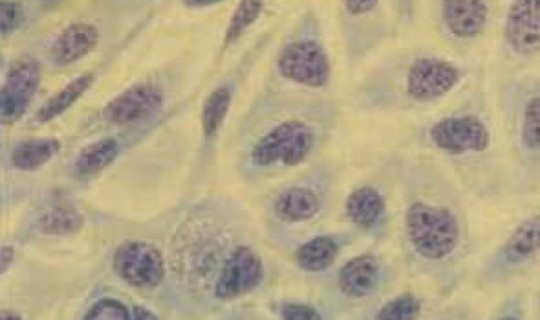

一、致女性生殖永久受损的性病:衣原体感染衣原体感染确实可能导致女性生殖永久受损。生殖道衣原体感染是一种可通过性传播的疾病,男女均...